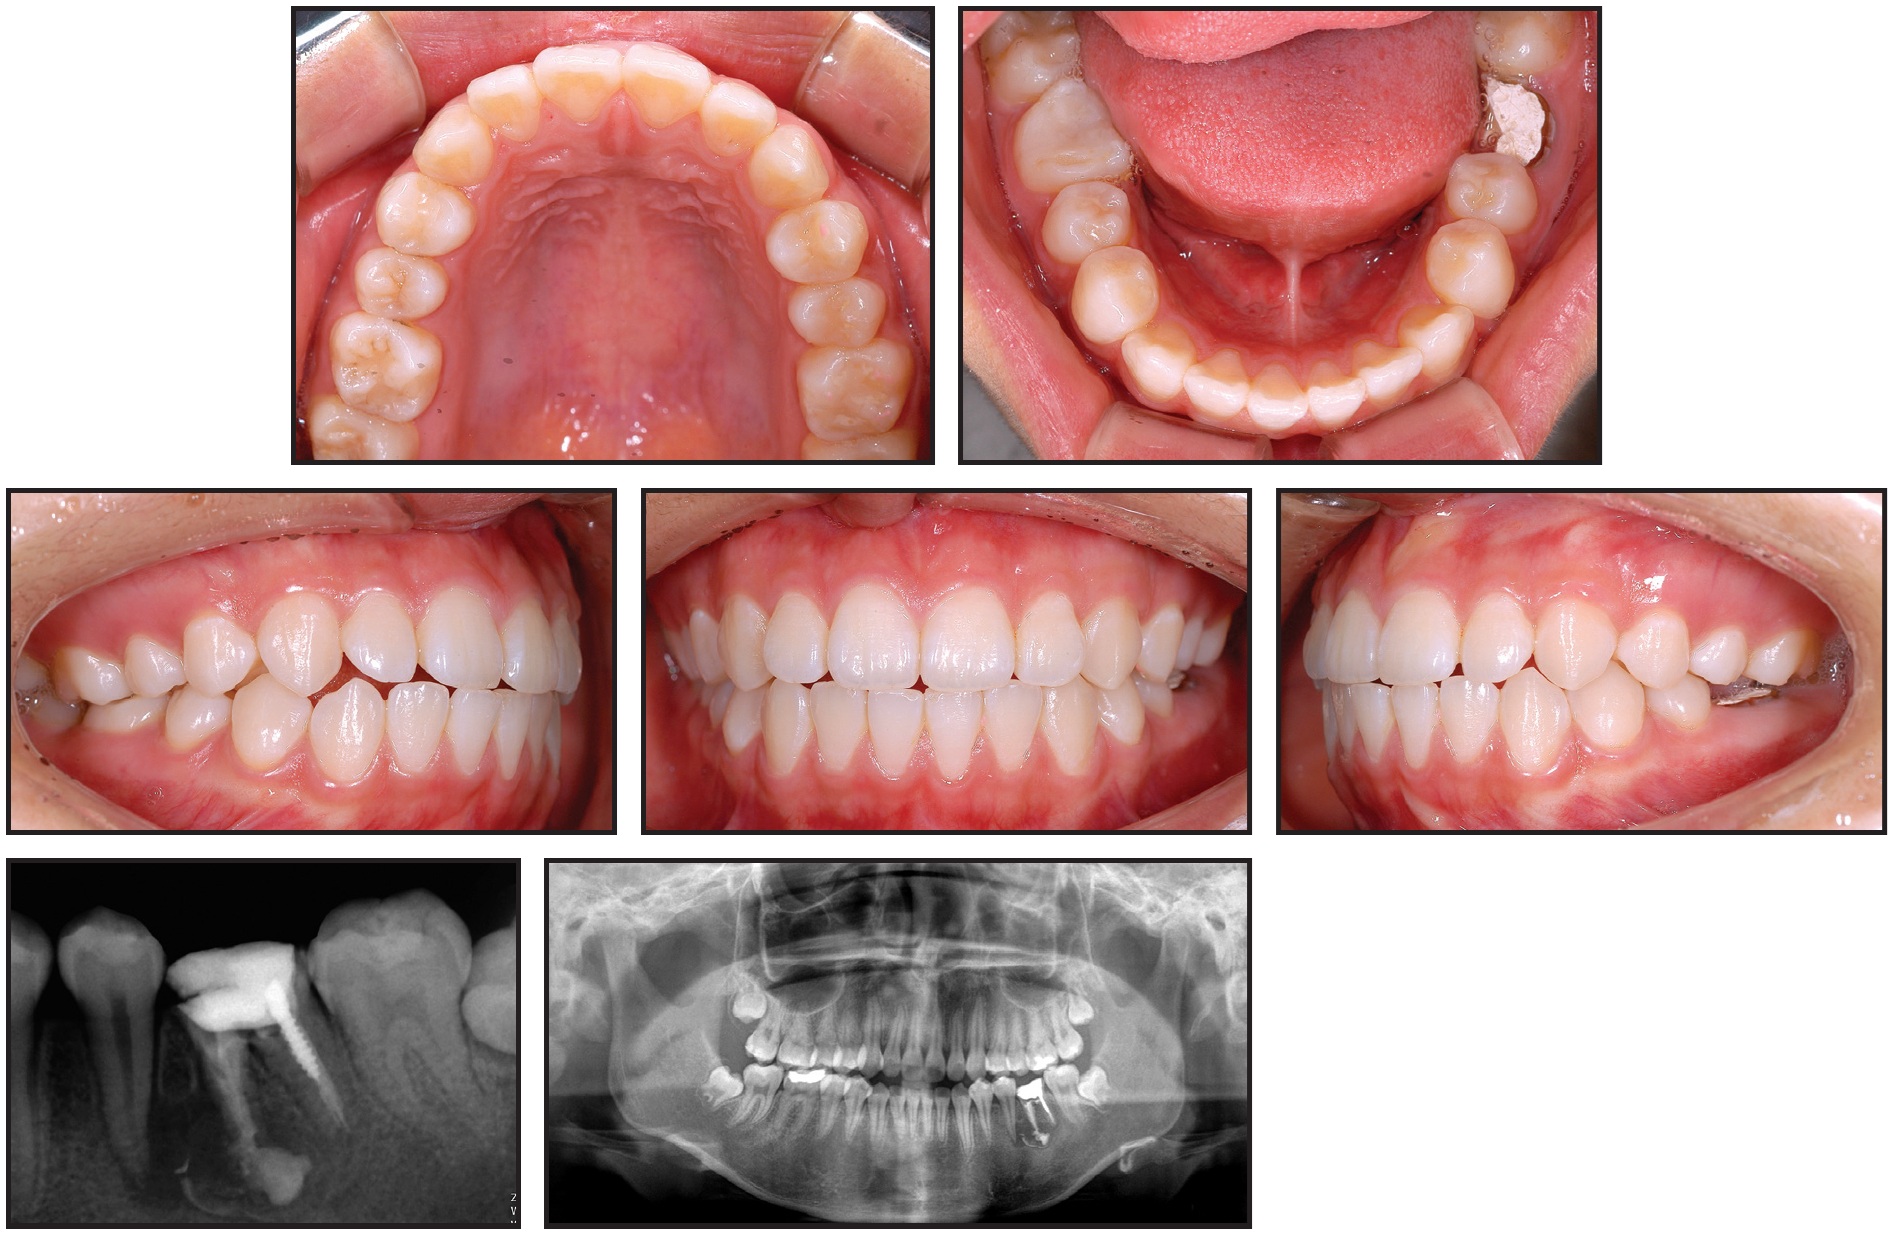

The lower second molar was slightly intruded by the sectional archwire, taking it out of occlusion (Fig. 3).

Fig. 3 Case 1. A. After two months of treatment, with first-molar mesial root remaining. B. Mesial root of first molar extracted after three months of treatment. C. After nine months of treatment, edentulous space almost closed.

After three months of protraction, the space created by extraction of the distal root was closed, and the mesial first-molar root was extracted. To prevent mesial tipping of the second molar, a tipback bend was made in the TMA wire. After nine months of treatment, the space was almost closed.

The third molar spontaneously moved mesially, following the protracted second molar. A gingivectomy was performed on the third molar, and a bracket was bonded for uprighting. After 16 months of treatment, the second and third molars were aligned into occlusion (Fig. 4).

Fig. 4 Case 1. A. Spontaneous mesial movement of third molar after 13 months of treatment. B. Three months later, molars aligned into occlusion.

After six months of retention, the micro-implants were removed (Fig. 5).

Fig. 5 Case 1. After six months of retention, favorable occlusion observed and micro-implants removed.

Records showed a well-maintained occlusion without root resorption or alveolar bone loss. The teeth displayed almost bodily movement without tipping, and no side effects, including alveolar bone atrophy, inflammation, soft-tissue clefting, or root resorption, were observed.